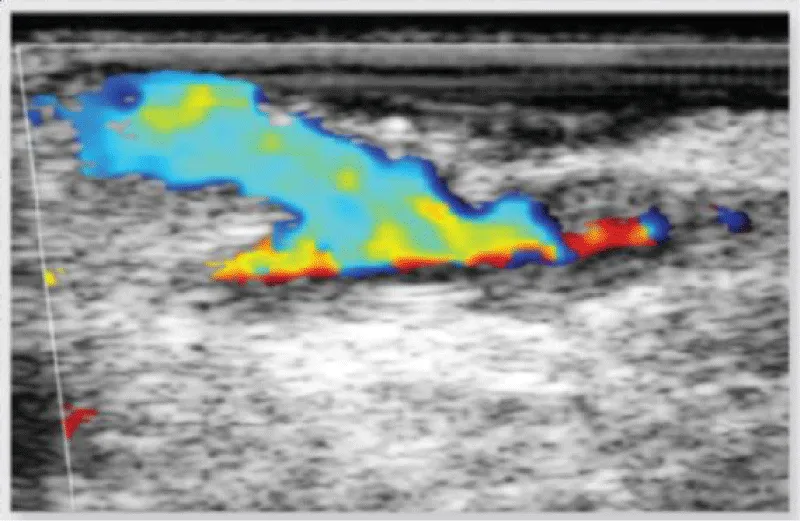

In case of obtaining dissenting values in comparison to the ideal measurement parameters or in case of doubt of the quality of the anastomosis performed, the epicardic echography presents as a valuable tool to provide a visual evaluation of the anastomosis, and sole the doubts (Figure 18).

Figure 18: Image of verification of an anastomosis between saphenous vein and marginal obtuse coronary artery, with Doppler echography, showing a decrease in the flow through the anastomosis due to the presence of a flap of the venous graft.